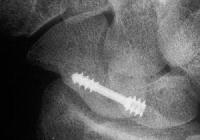

and two months postop:

Click for larger image